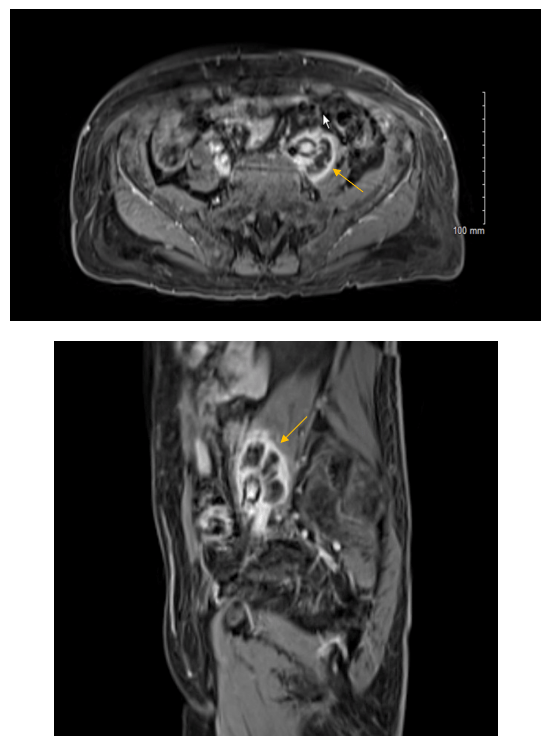

A 70 year old male with a past medical history of hypertension and non-invasive multifocal high grade papillary urothelial carcinoma was being followed closely for recurrence and underwent magnetic resonance imaging (MRI) of the abdomen and pelvis. The report described a 2.6 x 3.9 x 5.2 cm lobulated cystic mass involving the left psoas muscle. Furthermore, there was encasement of the left common iliac artery and less involvement of the left common iliac vein (Image 1). Further evaluation of the lesion was pursued to determine the etiology. An important aspect of this case to consider is the patient’s prior cancer treatment regimen, which included intravesical Bacille Calmette-Guerin (BCG) for 5/6 cycles. The final BCG treatment was held because the patient developed “BCG-osis” comprised of chest pain, rigors, chills and hypotension. Given the only pathology to date on the patient was non-invasive papillary carcinoma (even though it is high grade), the oncology group did not think the psoas muscle lesion was a metastasis. Fine needle aspiration (FNA) was pursued and the CT-guided aspiration demonstrated “abundant histiocytes and acute inflammation with necrotic debris…Acid fast organisms identified on AFB (acid fast bacilli) stain…Negative for malignant cells” (Image 2). Microbiology cultures were obtained at the time of FNA. The AFB smear showed 1+ AFB. AFB grew in culture and reacted with the Mycobacterium tuberculosis complex probe. The patient’s interferon gamma response assay (IGRA) was negative the year prior. Antimicrobial susceptibilities (AST) using the Mycobacterial Growth Indicator Tube system with single drug concentrations revealed susceptibility to isoniazid, rifampin, and ethambutol with resistance to pyrazinamide. Per protocol, the isolate was sent to a reference laboratory for identification which returned as BCG. During the interim, before AST was available, the patient was referred to our Infectious Diseases outpatient clinic where he was started on R(ifampin)-I(soniazid)-P(yrazinamide)-E(thambutol) therapy and then followed up his care with the county health department.